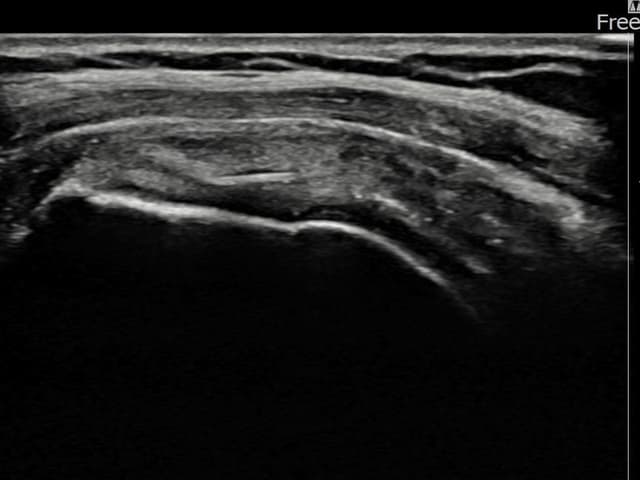

[촬영시기:22.10.06~22.11.14]

[어깨인대 축소봉합술] 좌측 어깨 극상근건 광범위 파열로 수개월간 일상생활이 어렵던 중 내원하셨습니다.